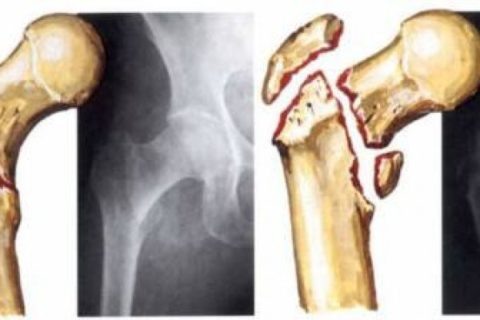

Суть операции заключается в репозиции отломков, остеосинтезе и устранении мелких осколков, если таковы имеются. Однако, даже если такие меры были предприняты в первые часы после получения травмы, могут возникнуть осложнения, которые потребуют более основательного вмешательства.

Наиболее часто при переломе шейки бедра костные отломки скрепляют специальными металлоконструкциями.